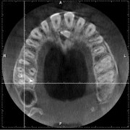

CTやレントゲンを使った徹底的な検査・診断・チェック

根管治療では、マイクロスコープや拡大鏡を使うことにより肉眼では見づらい根管をはっきり見ることができます。

しかし、複雑な歯の根の中を治療するには、それらだけでは万全ではありません。

当院では、CTやレントゲンを使って目に見えない部分の問題やポイントも見逃しません。

CTやレントゲンのデータは、治療前の徹底的な検査や診断に役立てるほか、治療後のチェックにも使用されます。

CT画像の例